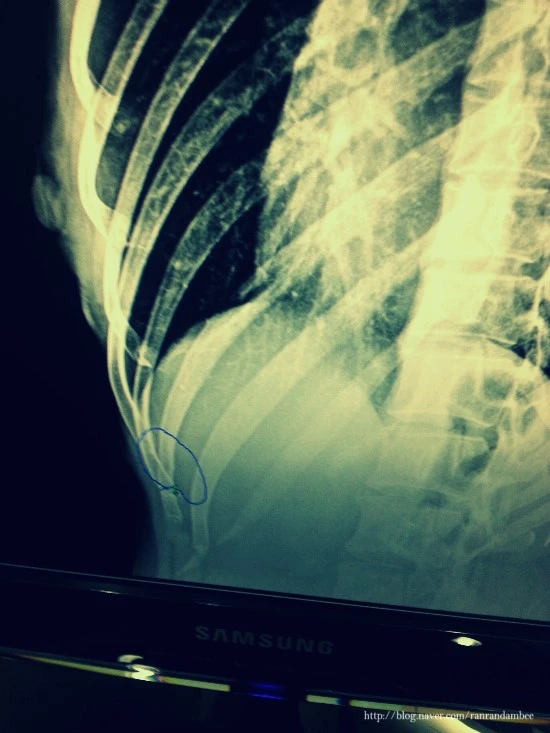

얼마 지나지 않아, 50대초반으로 보이는 남자의사 선생님 한 분이 들어오셨다. 그 분은 나의 CT사진을 자세히 보시다가 침착하게 말문을 열었다.

"그렇죠, 뼈가 부러졌으니.. 그런데 그동안 어떻게 참으셨어요?"

너무 기가 막혔다. 아무래도 난 바보가 맞나보다. 맹장수술을 받은지 얼마나 됐다고, 이젠 뼈까지 부러지다니.. 오른쪽 9번 갈비뼈..